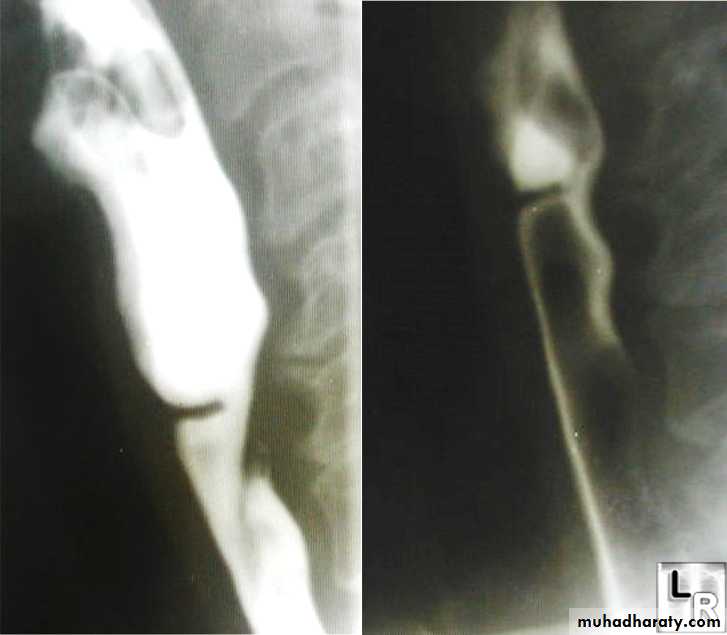

PULSION DIVERTICULUM

Due to:raised intra-luminal tension

Chocking after meal .

In cervical portion at level of C5

Posteriorly (Killience dehiscent)

Lateral view show increased pre-vertebral space with air fluid level.

Confirmed by Ba. Swallow.

TRACTION DIVERTICULUM

Out pouching of lumen laterally due to fibrosis & adhesions ( post-Tb.)

In the middle third at level of hilum

Up ward direction of diverticulum

Irregular base

On the far left a traction diverticulum (arrow) due to hilar granulomatous disease. Calcified adenopathy (asterisk).

In the middle a pulsion diverticulum (arrow) due to high intra luminal pressure.

On the right multiple pulsion diverticula (arrows)